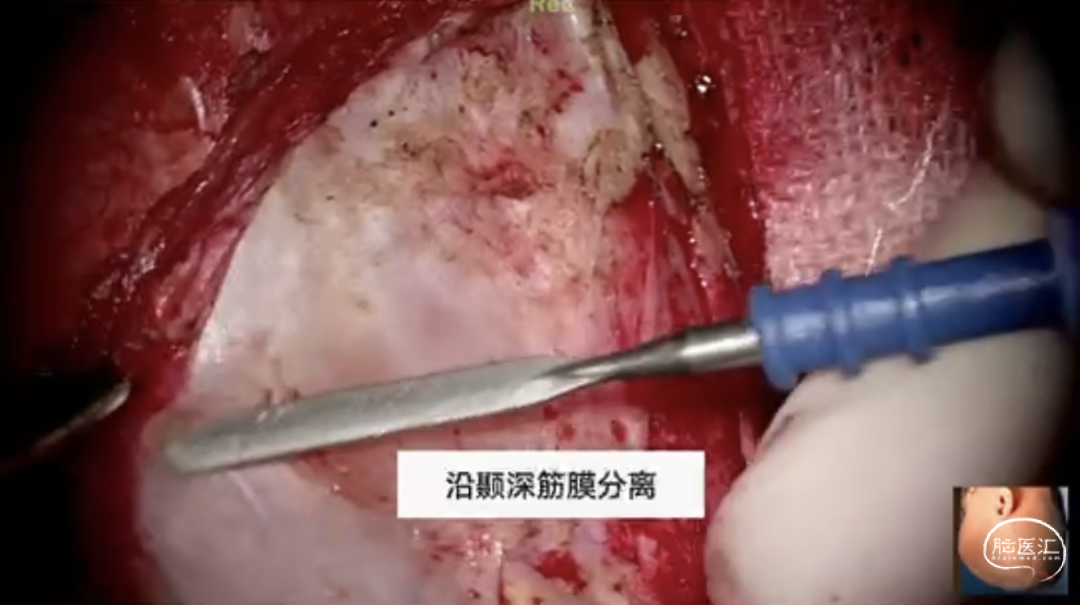

步骤二:分离颞肌,颞肌分离完毕后把颞肌翻开,充分暴露骨窗